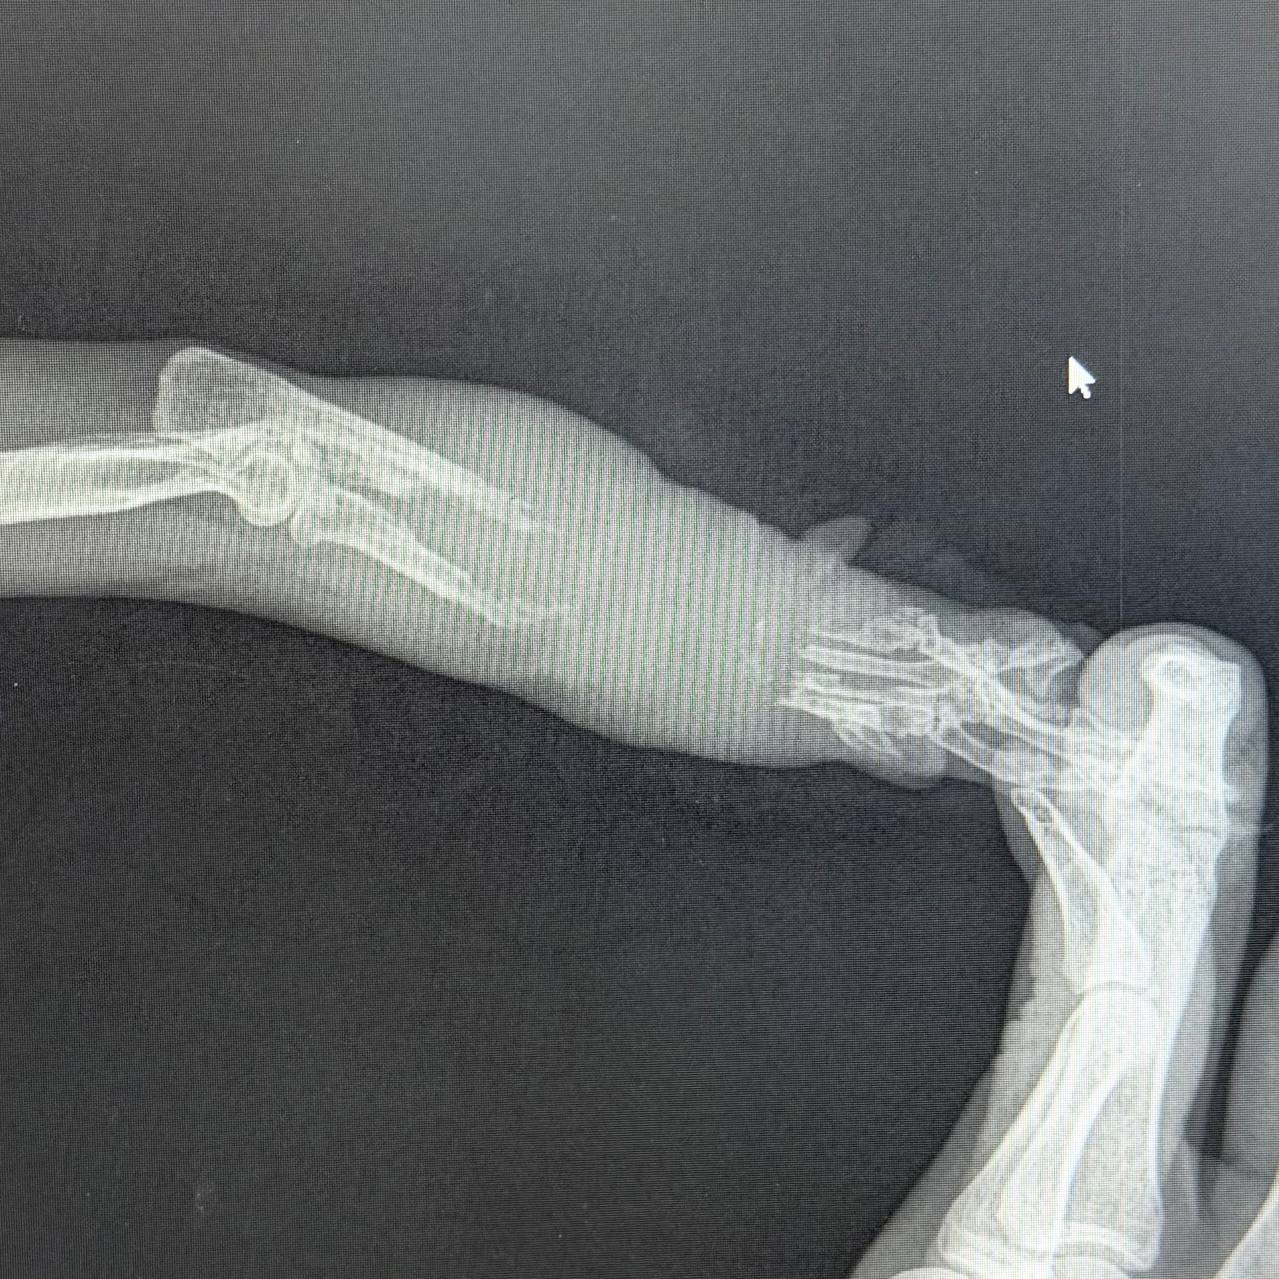

@tanya_auraУважаемые сочатовцы, разрешите рассказать вам историю кошки Сетки. Больше месяца назад, в центре Пафоса вдвоем с местным волонтером мы поймали кошку с поврежденной лапой. Кошка так боролась за свою свободу, что сетку сачка пришлось резать (к счастью обошлось без повреждений для кошки),а кошка получила свое нынешнее имя Сетка 😁. Дело было уже после 19 часов, и мы отвезли кошку в клинику, которая открылась по имердженси. Рентген показал, что часть кости просто исчезала, как будто растворилась 😥. Было подозрение на онкологический процесс, который, к счастью, не подтверждён. Лапу благополучно ампутировали. Операцию Сетка перенесла нормально. Сейчас место ампутации уже зажило, Сетку стерилизовали, ушко ей не обрезал, потому что на улицу ей точно нельзя🥹 Сетка получила первую вакцину и в данный момент проходит социализацию на бесплатной передержке! Очень прошу вас помочь с оплатой счета Сетки, даже несколько евро очень помогут!🙏 Револют для сбора предоставила @tuewbs https://revolut.me/tuewbs/pocket/ss3ubHq7PT